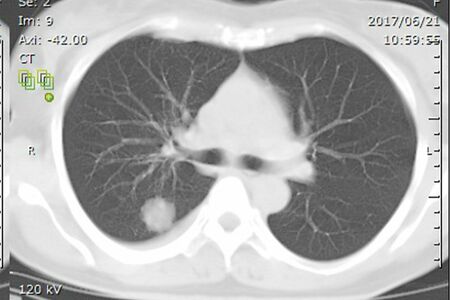

肺がんの主な組織型(がんの種類)は4つあり、松本さんが罹患したのは、肺がんの中で最も多い腺がん。女性に多く、喫煙しているかどうかは関係なく発症するといわれている。今後の治療方針は、遺伝子変異の有無など、さらに詳しい状態がわからなければ決定できない。そのため、検査結果が出るまで4週間待つ期間があった。

検査の結果、松本さんの肺腺がんにはALK(アルク)融合遺伝子という遺伝子変異が認められ、分子標的薬による薬物療法を行うことが決定。

薬の効果でみるみる腫瘍が縮小し、2週間後に退院。その後1週間の自宅療養を経て仕事にも復帰した。